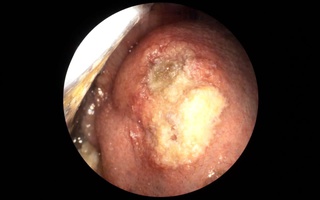

Viêm xoang bướm do nấm âm thầm tấn công người bệnh

(NLĐO ) - Bệnh viêm xoang bướm do nấm có triệu chứng mơ hồ, không điển hình, dễ nhầm với viêm xoang mạn thông thường.